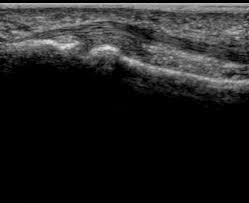

To describe clinical findings, ultrasonographic features and outcome of injury to the branches of insertion of the superficial digital flexor (sdf) tendon in horses.

Fourteen thoroughbred horses with tendonitis affecting the branches of insertion of the sdf tendon were examined for lameness, location and amount of swelling, and the. The fdp tendon is the sole tendon responsible for dip flexion of the finger. A = annular pulley, c = cruciate pulley figure 1 a, vincular blood supply. It is in the anterior compartment of the forearm. The vascular anatomy of the flexor digitorum profundus (fdp) tendon insertion is described by using a vascular injection and modified spalteholtz tissue clearing protocol in 36 human cadaver digits. Since the ring finger protrudes the farthest in the grasping position, it is more susceptible to fdp avulsion causing an inability to flex at the dipj[1]. The split tendon of flexor digitorum superficialis reunites deep to the tendon of flexor digitorum profundus, around which it forms a loop. Ebraheim's educational animated video describes the anatomy of the flexor digitorum profundus muscle.the flexor digitorum profondus is a muscle in the fo. The fds is in red, the fdp in yellow. Jersey finger (rugby finger) is an avulsion of the flexor digitorum profundus tendon (fdp) from its distal insertion on the distal phalanx (zone i). Flexor digitorum superficialis (flexor digitorum sublimis) is an extrinsic flexor muscle of the fingers at the proximal interphalangeal joints. Rupture of the flexor digitorum profundus (fdp) tendon from its distal attachment is commonly known as jersey finger. Retrospective study of 14 cases.